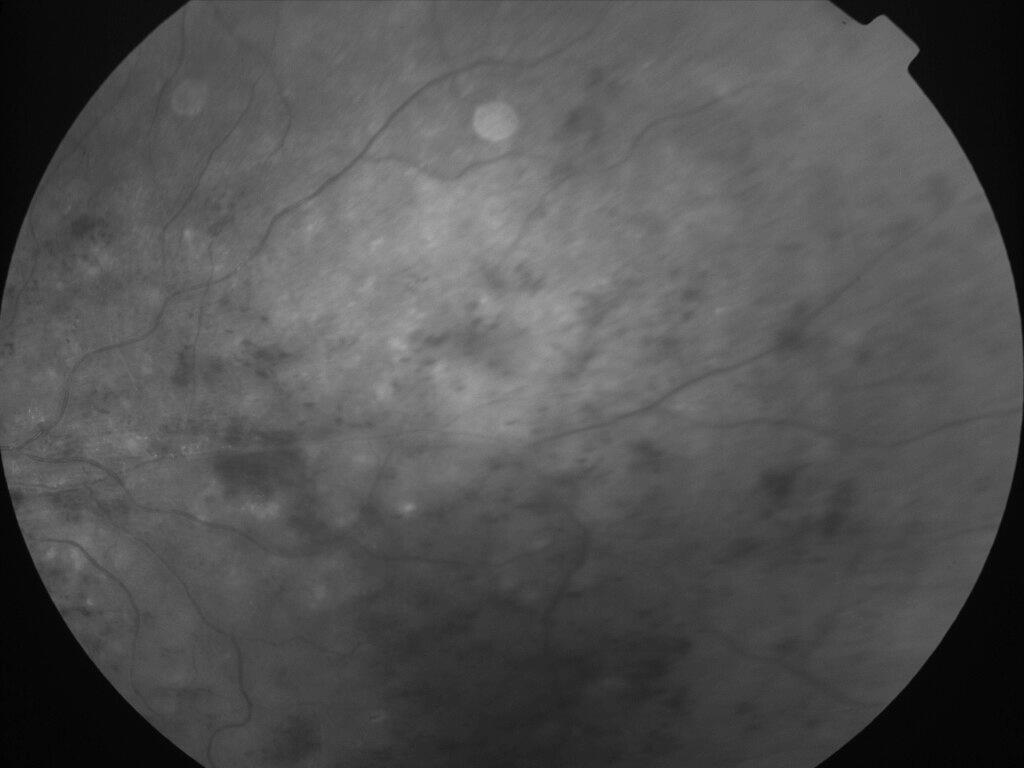

OCCLUSION DE BRANCHE DE LA VTS DE FORME ISCHEMIQUE MAJEURE